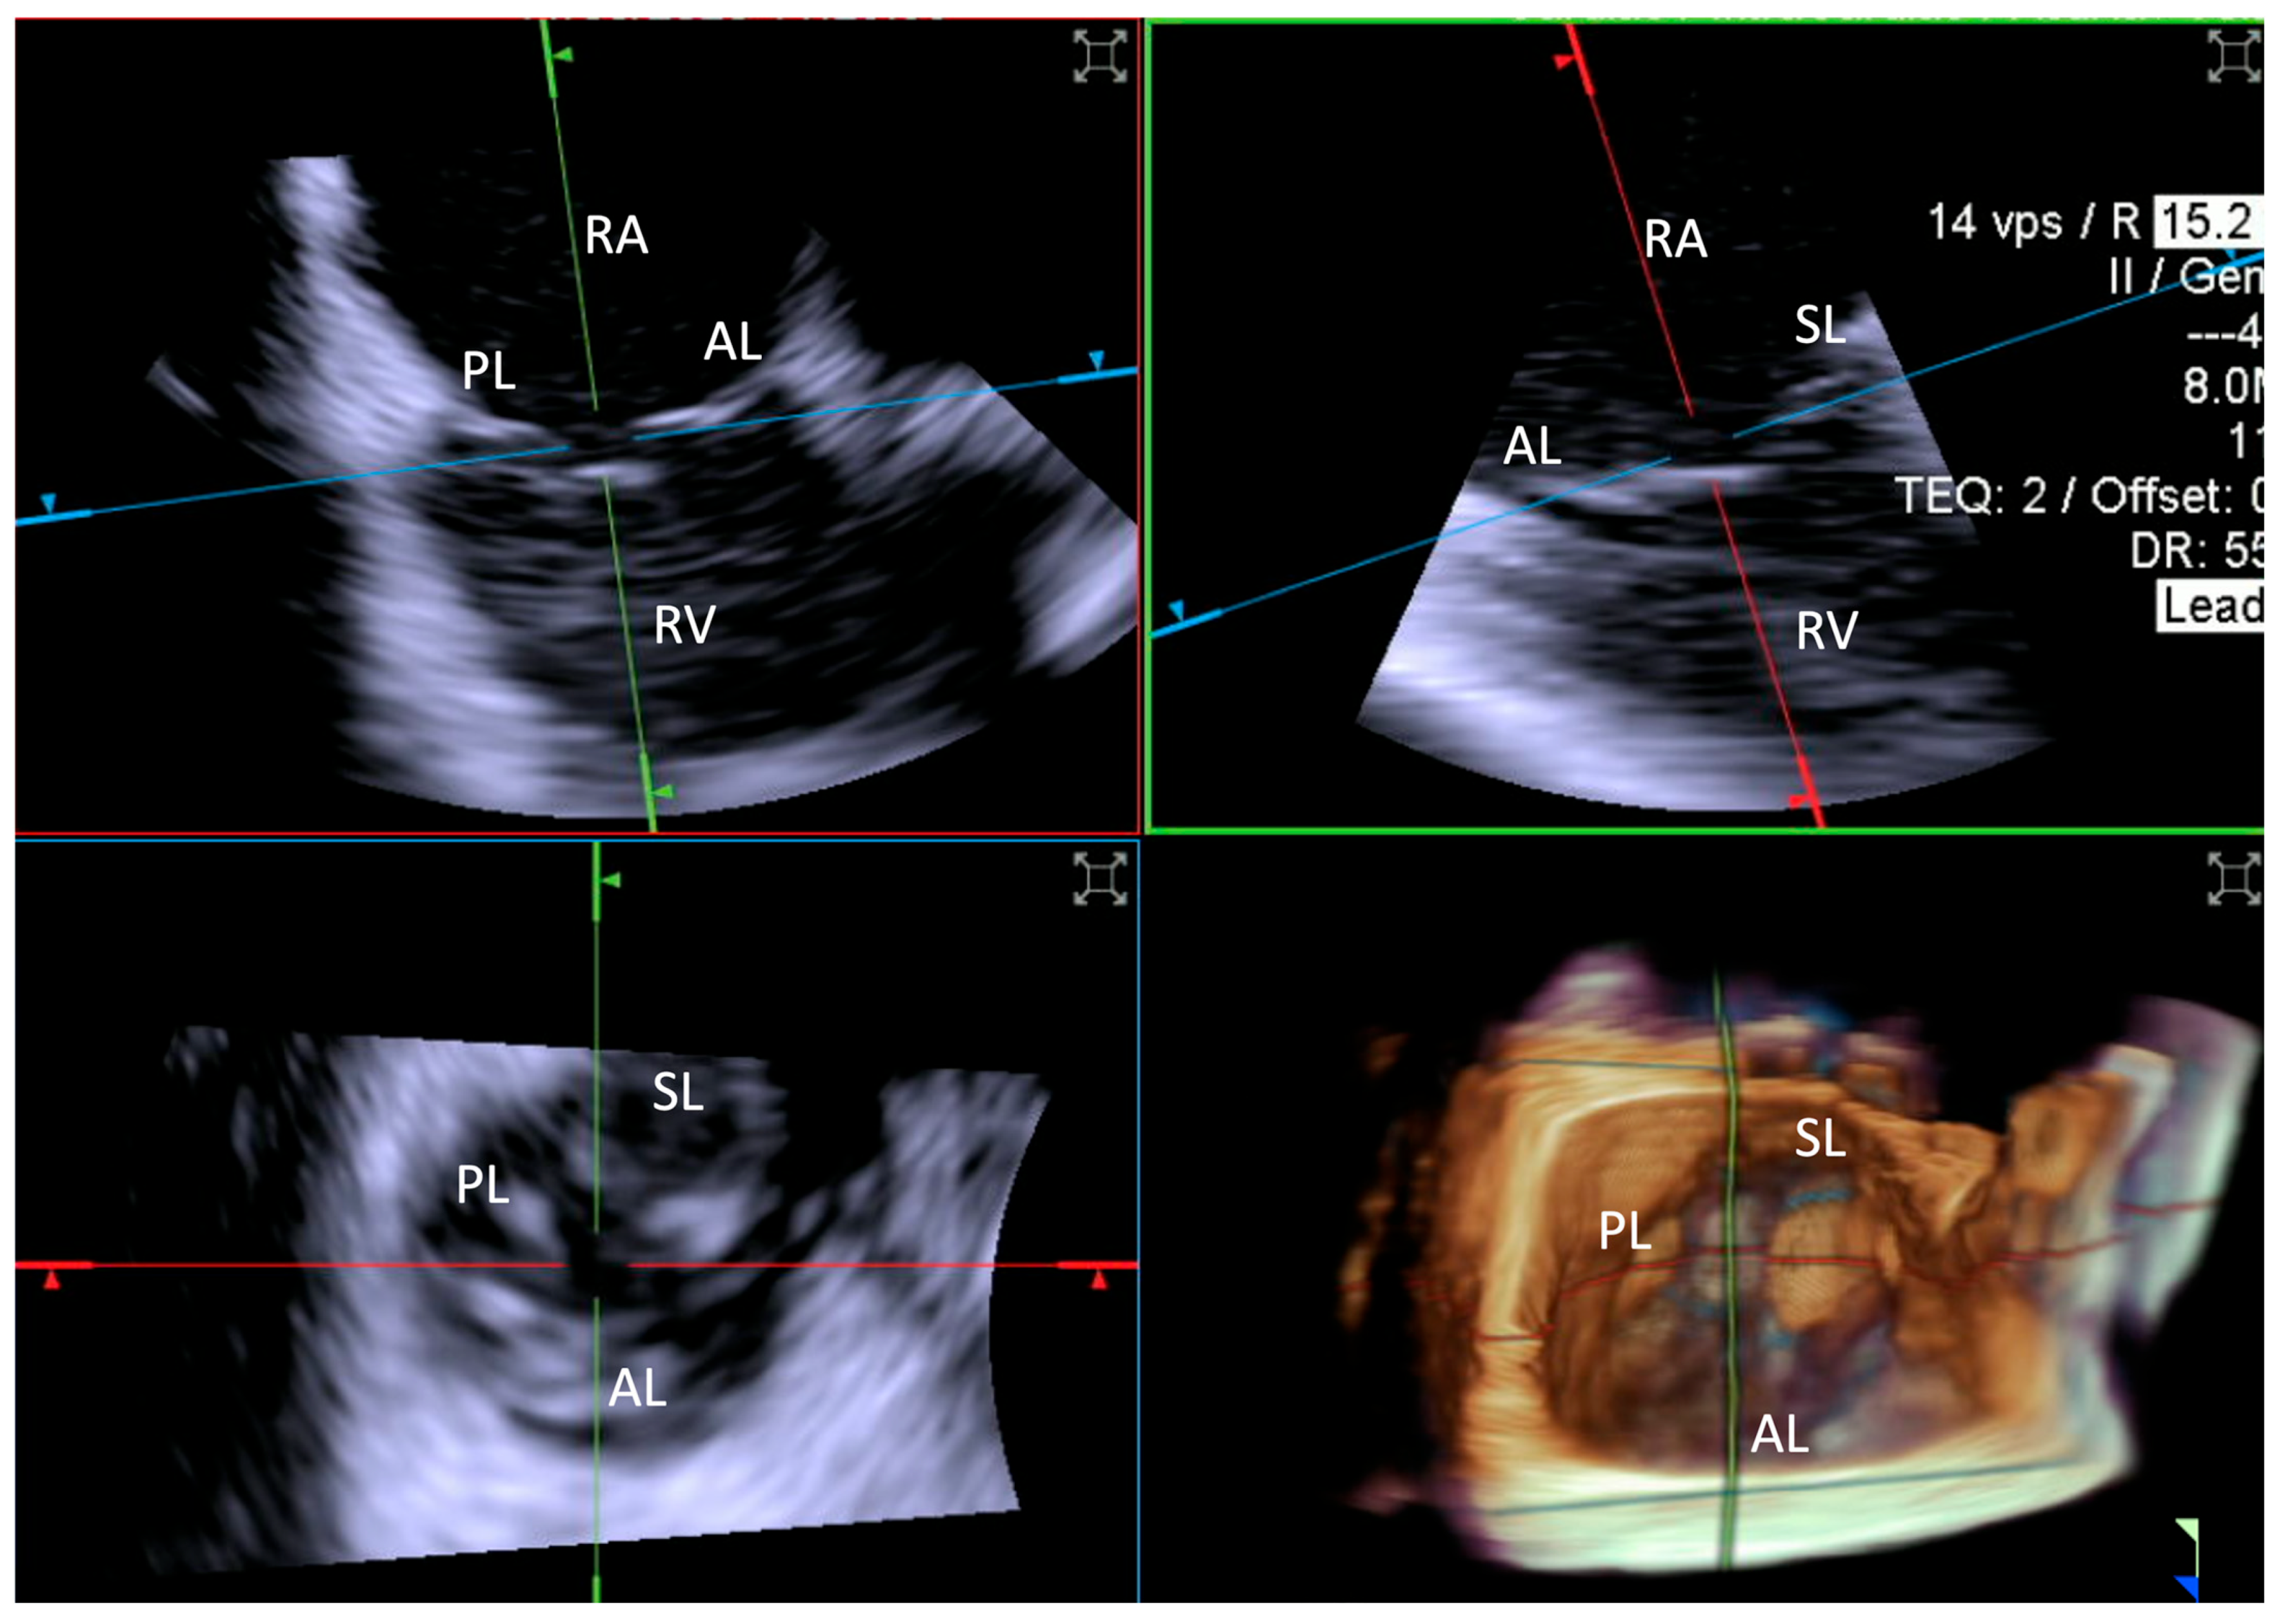

- Step number 1: assessment of tricuspid valve anatomy.

3.3.1. Step-by-Step Evaluation